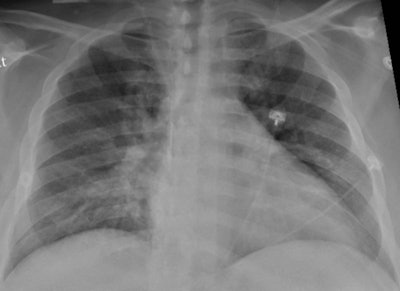

SARS-CoV-2, the virus that causes COVID-19 disease, first affects patients' respiratory systems, Freeman and colleagues noted. But it has increasingly been shown to affect many other body systems as well, including the brain.

To investigate the incidence of critical findings in COVID-19 patients with additional disease, the team conducted a study that included 81 patients who underwent head CT and/or MRI between January and April of this year, indicated by altered mental state or speech or vision difficulties. Seventy-one patients had head CT scans, one had a brain MRI scan, and seven had both exams. Mean age of the patient cohort was 66.

Of these 81 participants, 18 had findings on brain imaging that were categorized as critical, such as strokes, brain bleeds, blocked vessels, or encephalopathy. Of those with critical imaging findings, 72.2% had high blood pressure and 50% had type 2 diabetes; many had elevated blood markers of inflammation (creatinine, D-dimer, and fibrinogen).